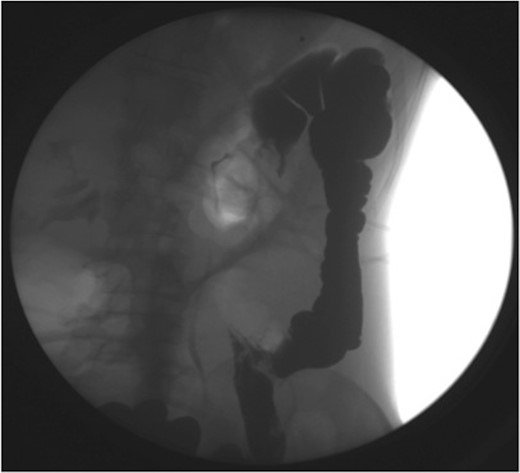

Haemoglobin was 14.9 g/dl and the white cell count (WCC) was 9 × 109/l. Other remarkable laboratory tests included a C-reactive protein (CRP) of 15 mg/l. Urinalysis was normal. The plain X-ray abdomen (AXR) (Fig. 1) revealed dilatation of a focal segment of large bowel with mildly dilated small bowel. Computed tomography (CT scan) of his abdomen reported that the gas-filled viscus is likely to represent the caecum (Fig. 2).

CT of the abdomen (Case 1) demonstrating the gas-filled caecum.